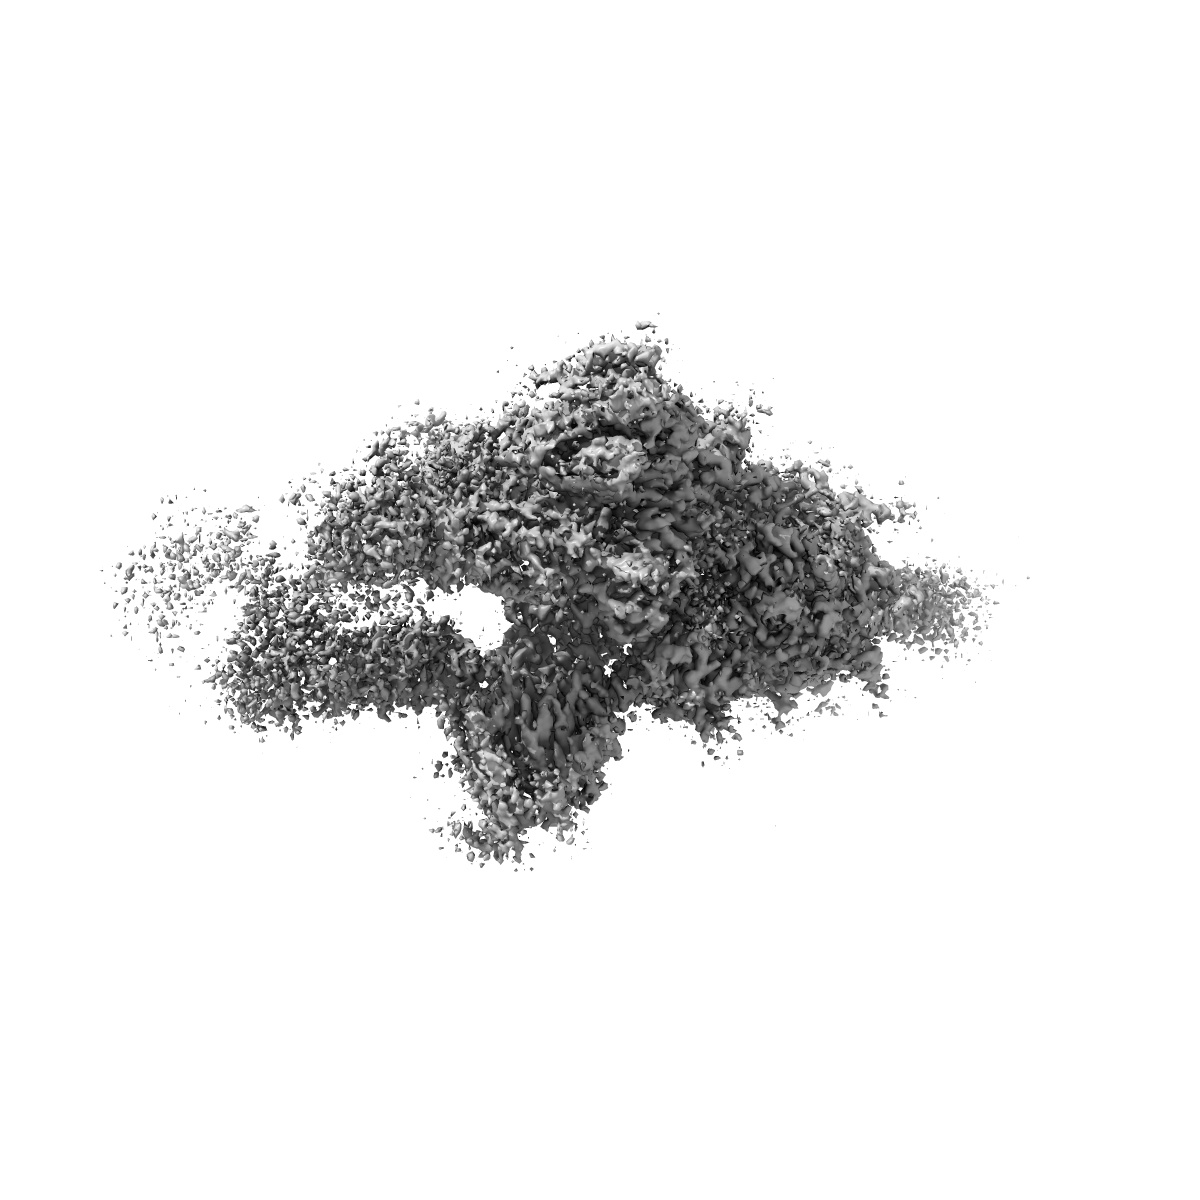

EMD-30516

S protein of SARS-CoV-2 in complex bound with P5A-2G9

Single-particle2.7 Å

Structural basis for bivalent binding and inhibition of SARS-CoV-2 infection by human potent neutralizing antibodies.